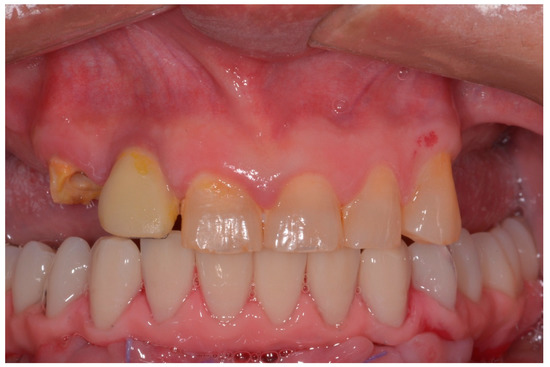

Six months after surgery, all temporary restorations were replaced with final prosthetic restorations (Figure 7).

Figure 7. 2 years postoperative panoramic X-ray.